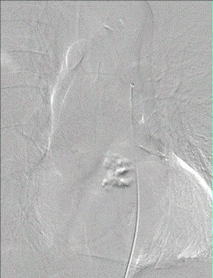

Figure 1. Type I Spinal Dural Arteriovenous Fistula - Spinal angiogram (left image) of a left sided spinal segmental artery (white arrow) with an abnormal connection (red arrow) to a spinal cord vein that has become abnormally enlarged (blue arrow)

- These malformations represent 70% of spinal vascular malformations and are the result of an abnormal connection forming between an artery and a vein in the spinal canal dural covering (Figure 1). This connection allows high pressure arterial blood to escape into the low-pressure network of spinal cord veins. Over time, the spinal cord is damaged by the elevated pressure in the veins. Spinal dural arteriovenous fistulas (AVFs) are thought to form spontaneously during adulthood and are not congenital or hereditary. These lesions rarely rupture or bleed, but they do cause significant spinal cord dysfunction that can result in leg weakness, lower body numbness, imbalance, and urinary problems. These malformations are good candidates for surgical treatment and endovascular treatment, which are typically curative.